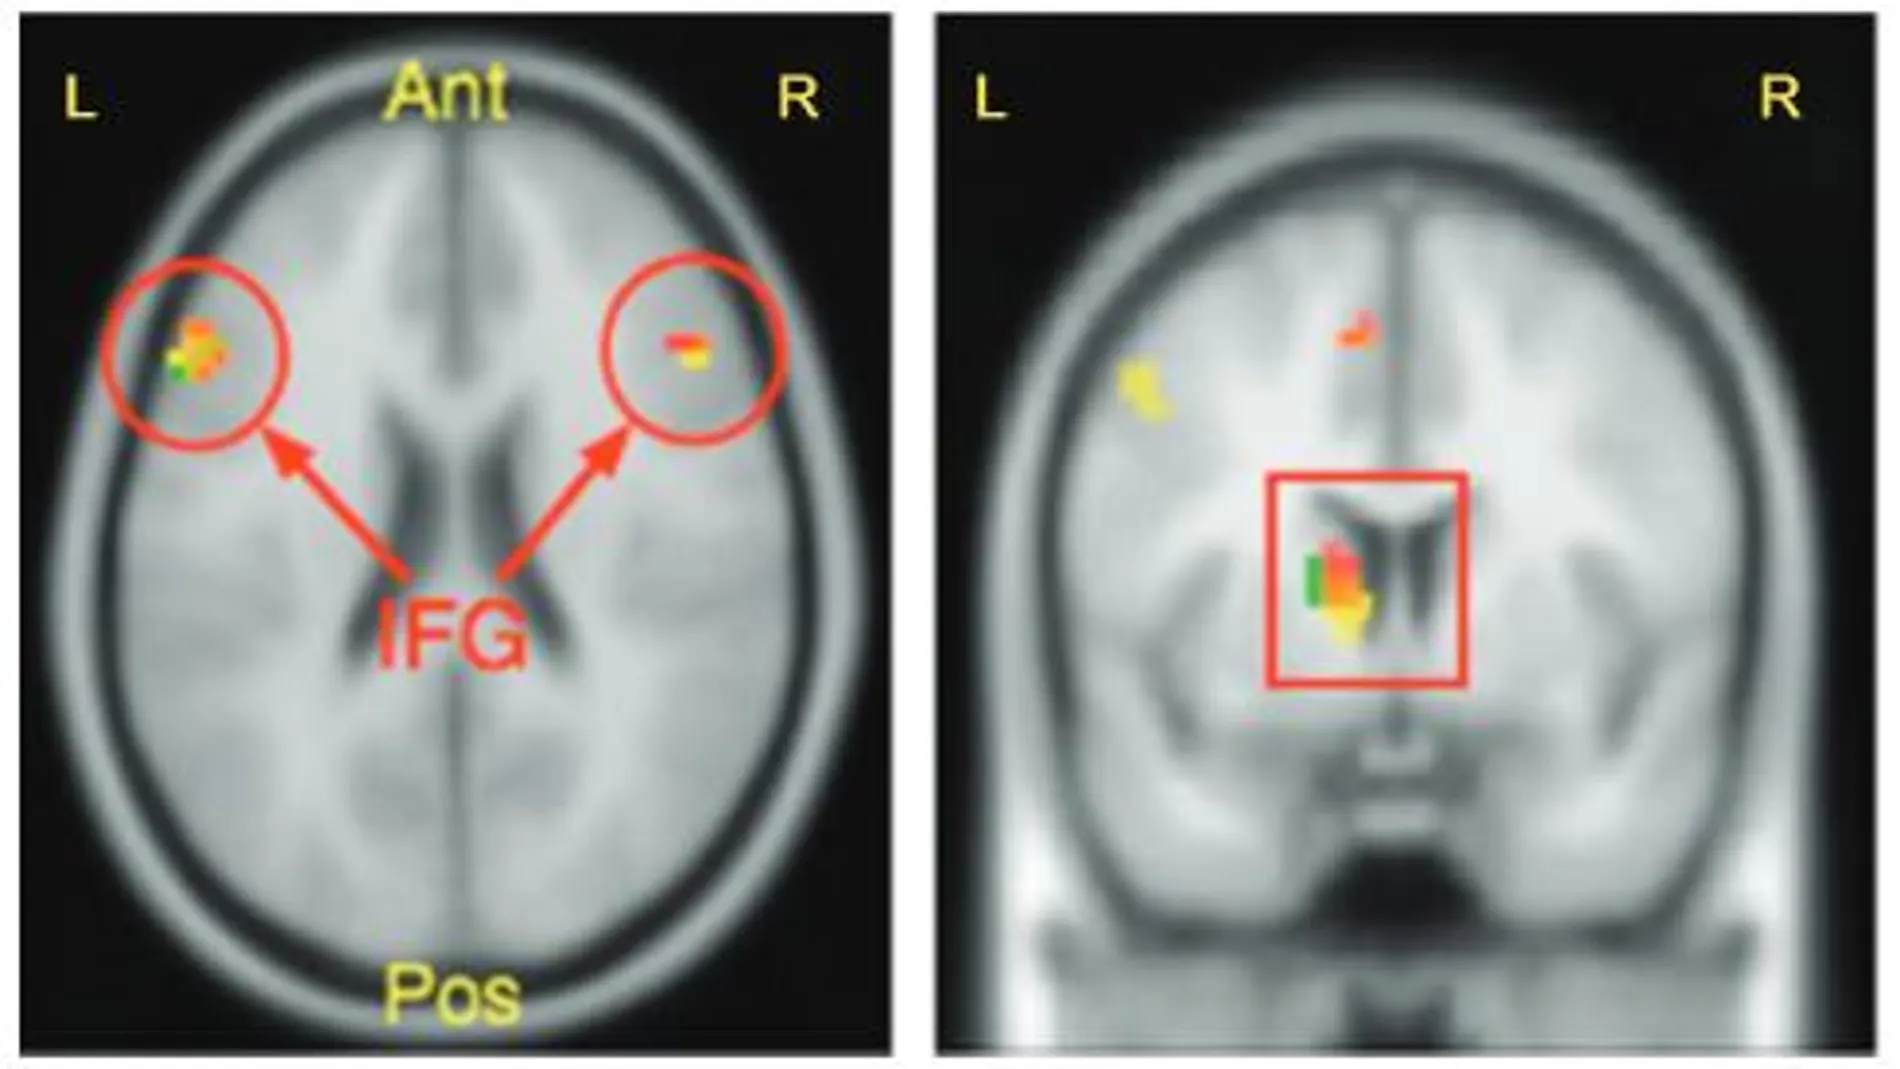

Diferentes trabajos han demostrado las bases neurológicas de este escurridizo concepto. Cuando tratas de dar con la respuesta de algo que desconoces, en tu cerebro se activan al menos dos áreas cerebrales: una relacionada con la motivación y la recompensa (ubicada en el estriado ventral) y otra implicada en la memoria (el hipocampo).

Camerer y un equipo de científicos utilizaron imágenes de resonancia magnética para averiguarlo. Según su estudio, en aquellos participantes curiosos que aprendían algo nuevo se intensificaba la actividad en las áreas del hipocampo relacionadas con la consolidación de la memoria, por lo tanto, demostraron que aprender algo motivado por la curiosidad mejora nuestra capacidad de recordar.

“La curiosidad es la forma que tiene el cerebro de marcar la información que merece la pena recordar”, destaca el investigador. Las imágenes cerebrales revelaron también que cuando los participantes fallaban una respuesta, se incrementaba la actividad en las áreas cerebrales de la memoria, puesto que estaban preparándose para conocer la respuesta correcta y retenerla, lo que parece indicar que la curiosidad mejora la memoria cuando la información nos sorprende.